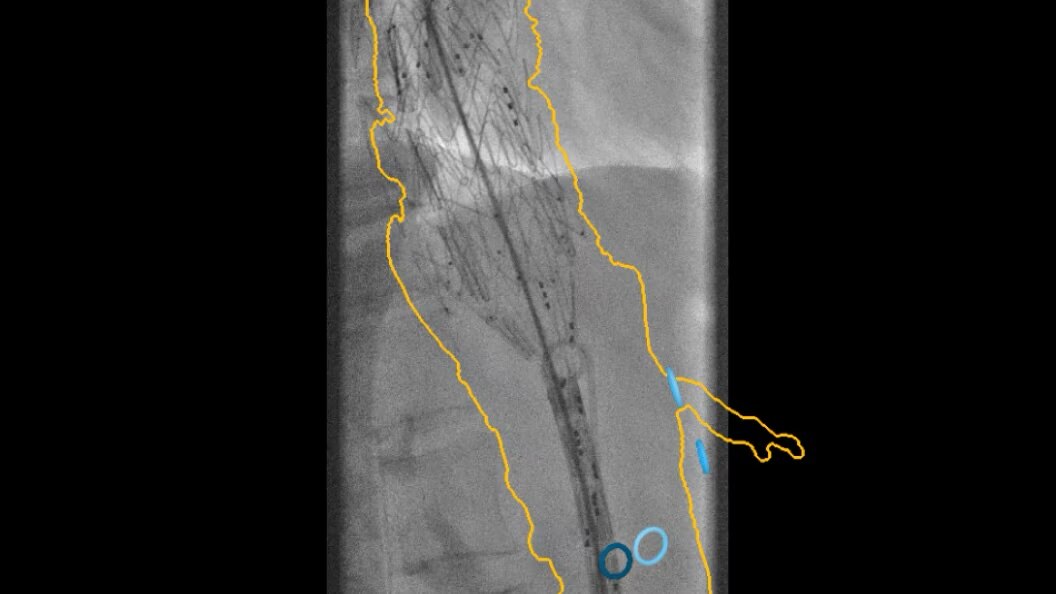

Cone-Beam Computed Tomography

Experience the precision of cone-beam CT, offering high-resolution 3D imaging for accurate diagnostics and treatment planning with enhanced safety and efficiency.